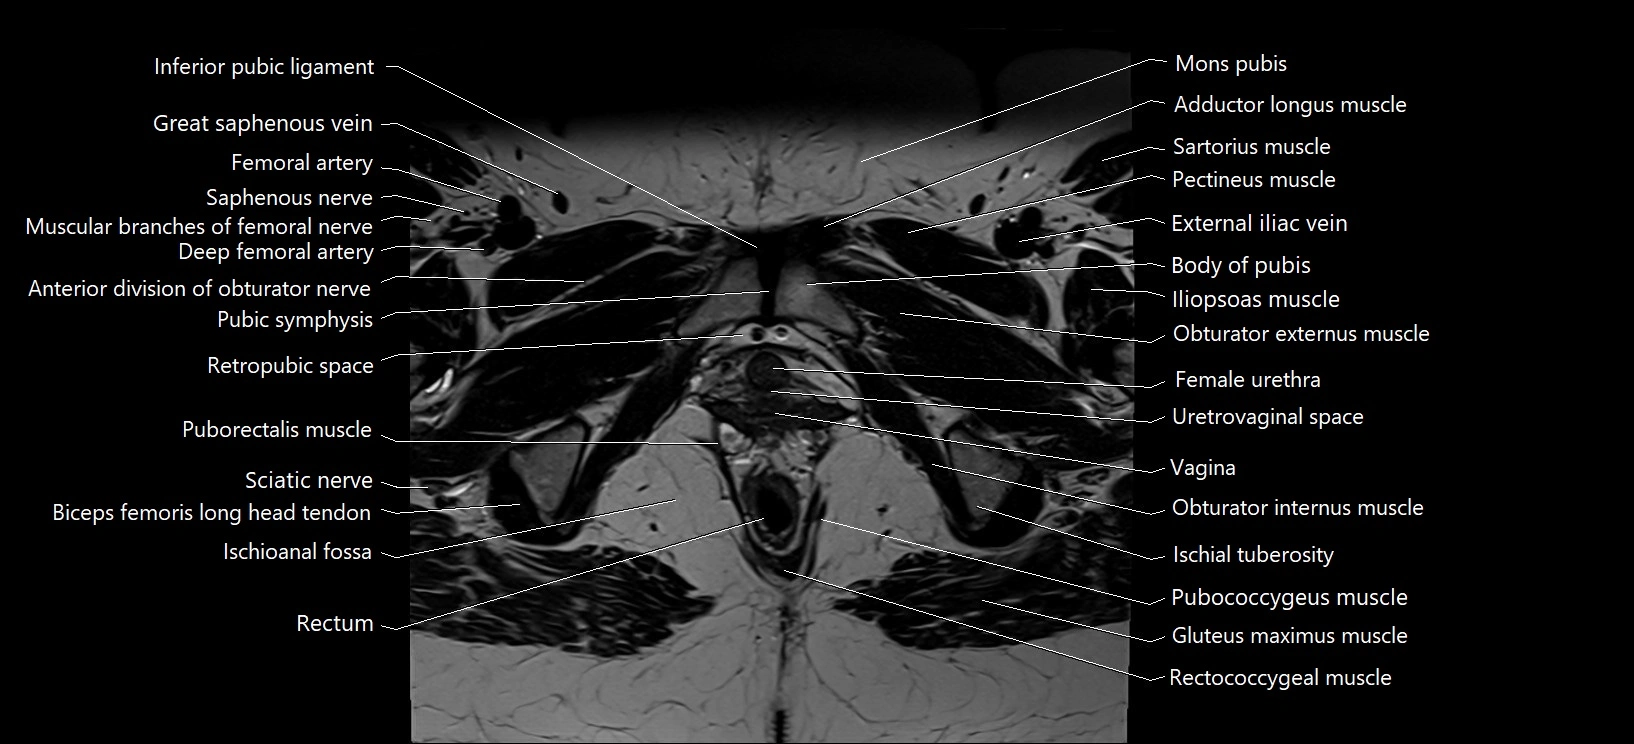

- Body of pubis

- Deep femoral artery (profunda femoris)

- Female urethra

- Inferior pubic ligament

- Ischioanal fossa

- Pubic symphysis

- Puborectalis muscle

- Retropubic space

- Saphenous nerve

- Sciatic nerve

- Vagina